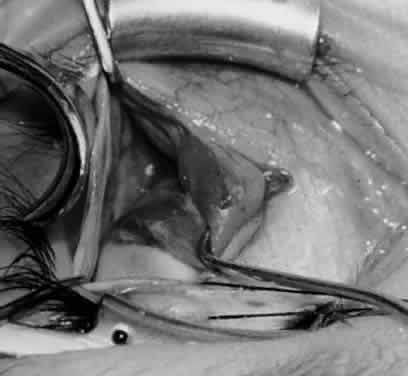

Fig. 1. The standard inferior-temporal fornix incision is made through the conjunctiva and Tenon's capsule with a Westcott scissors. The incision is placed about 8 mm posterior to the limbus, anterior to the fat pad.

Fig. 2. After the lateral rectus muscle is hooked with a Stevens and then a Green muscle hook, the lateral rectus muscle is tented to allow placement of a 4-0 silk suture beneath the insertion of the lateral rectus muscle. The needle tip should glide along the inferior surface of the muscle hook to avoid laceration of the lateral rectus muscle or laceration or penetration of the globe.

Fig. 3. The eye is retracted superonasally with the 4-0 silk traction suture. The suture is attached to the drapes with a hemostat. A Stevens hook is placed along the inferior border of the lateral rectus muscle and drawn temporally. A von Graefe hook is placed within the incision and drawn inferotemporally to expose the inferior oblique muscle.

Fig. 4. A stiff iris repositor can be placed against the sclera to depress the sclera and enhance the view of the inferior oblique muscle. The inferior temporal vortex vein adjacent to the Stevens hook is retracting tissue along the inferior border of the lateral rectus muscle. The second Stevens hook is pointing to the inferior oblique muscle.